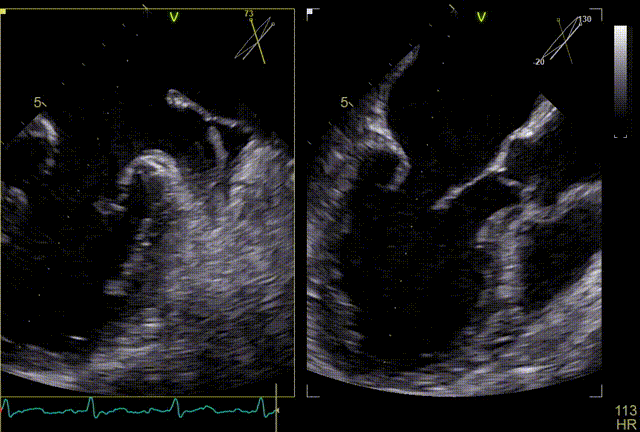

术前行经食道超声评估

原发性二尖瓣反流,反流程度4+;二尖瓣瓣口面积4.15cm²,平均跨瓣压差5mmHg,二尖瓣前叶(A2)长度23.35mm,二尖瓣后叶长度(P2)长度13.2mm;左室射血分数67%。患者手术风险高,操作难度大,经心脏瓣膜团队多次充分讨论评估后,决定行经导管二尖瓣缘对缘修复治疗。

术前MDT策略:从解剖结构来看二尖瓣后叶脱垂伴连枷涉及整个2区,累及3区和1区,宽度15mm左右,且连枷高度甩起高度有7-8mm,可见长达10.4mm的飘样回声,术前策略预计使用两个二尖瓣夹,较小的二尖瓣口面积和较高平均跨瓣压差,是一次高难度的挑战。